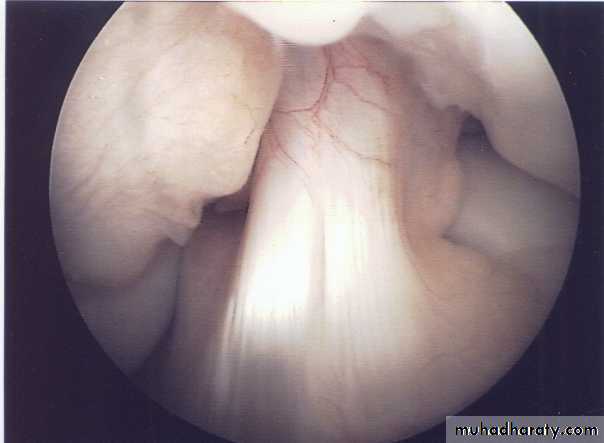

• Arthroscopy; it’s the best to give direct visualization of the inside of the joint to prove the diagnosis & exclude other possible injuries.

Arthroscopy can prove the diagnosis & show the site & type of the tear. Conservative treatment is only indicated for peripheral tears where the vascular meniscus may heal if the knee is rested for 3-4 weeks in POP or if the meniscus is sutured.Otherwise operative treatment is always indicated by arthroscopy, the aim is to excise the torn part of the meniscus only & leave the remaining intact part to avoid later degenerative changes of the knee.